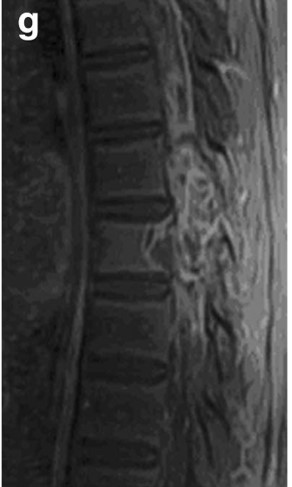

• CT

• STIR

• 左:CT(骨条件)、右:造影CT

• T1WI、T2WI、Gd-T1WI